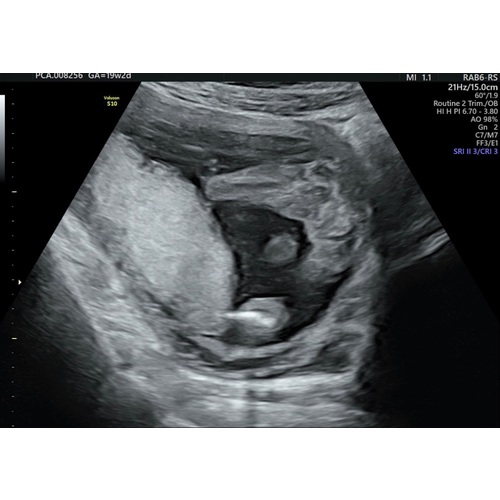

Dit is met de 20weken echo en we krijgen een jongen 💙🥰

Deze is inderdaad super duidelijk!